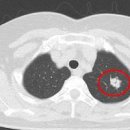

고립성 폐결절 및 흉부 전선량 폐 CT에 대한 와 설명 고립성 폐결절이란 폐 안에 혼자 떨어져 있는 작은 혹이나 덩어리를 말합니다. 크기가 작아 이 없는 경우가 많아 건강검진에서 우연히 발견되는 경우가 많습니다. 흉부 전선량 폐 CT는 폐에 대한...